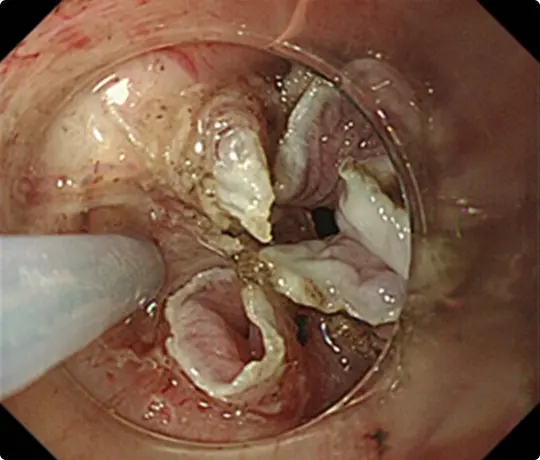

約3cmの大きな大腸ポリープです。

スネアでポリープの根元を縛り、電流を流して切除します(出血予防のためポリープの根元にクリップをうっています)。

切除した検体です。病理検査で早期大腸がんと診断されました。がんは完全に切除されており、治癒と判定されました。